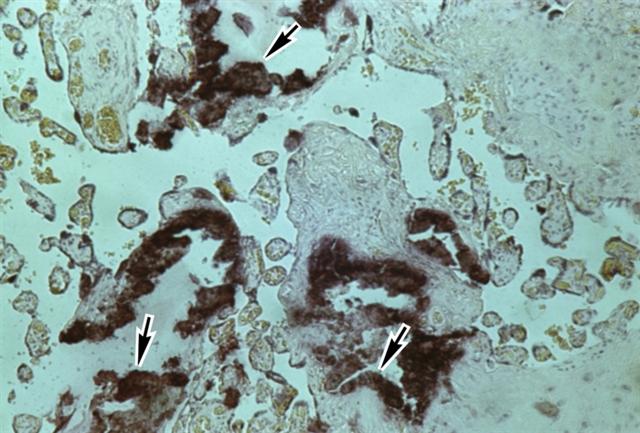

Рис. 4б). Микропрепарат дистрофически измененной плаценты при доношенной беременности: отложения солей кальция (указаны стрелками); окраска гематоксилином и эозином; ´65.